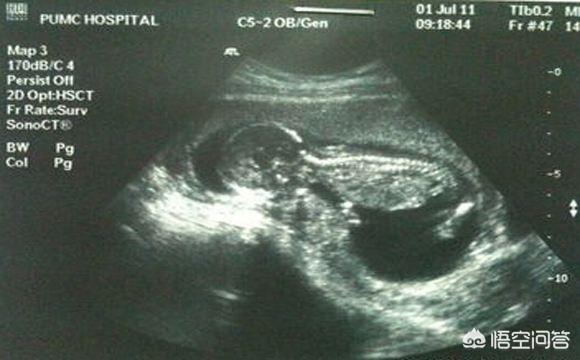

Beim B-Ultraschall werden im Allgemeinen die Entwicklung des Fötus und die Lage der Plazenta untersucht, selten geht es um fötale Erkrankungen. Nur beim 4D-Ultraschall werden fötale Fehlbildungen festgestellt, so dass es sich bei Ihrer Frage um den 4D-Ultraschall und nicht um den B-Ultraschall handeln sollte.

Mit dem Ultraschall kann überprüft werden, ob die Lage des Fötus normal ist, ob das Fruchtwasservolumen abnormal ist, ob die Nabelschnur des Fötus um den Hals gewickelt ist, ob die Entwicklung des Fötus verzögert ist und ob die Plazenta niedrig ist.

Der 4D-Ultraschall ist eine verbesserte Version des B-Scan-Ultraschalls, mit dem fetale Fehlbildungen, fetale Gesichts- und Körperorgane, Fehlbildungen der Gliedmaßen, wie z. B.: fetale Lippenspalte, Syndaktylie, vierfache Herzkammern, viszerale Ektopie,... erkannt werden können.

Die Ultraschalluntersuchung während der Schwangerschaft kann vor allem das Wachstum und die Entwicklung des Fötus, seine physiologische Aktivität, die Menge des Fruchtwassers und den Zustand der Plazenta feststellen.

Ein 4D-Ultraschall während der Schwangerschaft kann den Fötus auf angeborene Herzfehler, Hydrocephalus, Lippen- und Gaumenspalten und die Entwicklung der Gliedmaßen untersuchen. Der 4D-Ultraschall kann auch das bewegte Bild des Fötus im Körper der Mutter zeigen.

Der Ultraschall (4D-Ultraschall) ist ein notwendiger Bestandteil des Schwangerschaftstests, der vor allem für die Untersuchung der Körperoberfläche des Fötus und verschiedener Organe auf Fehlbildungen zuständig ist. Zum Beispiel: fötales Herz, Gehirn, Niere und andere Teile der Krankheit.